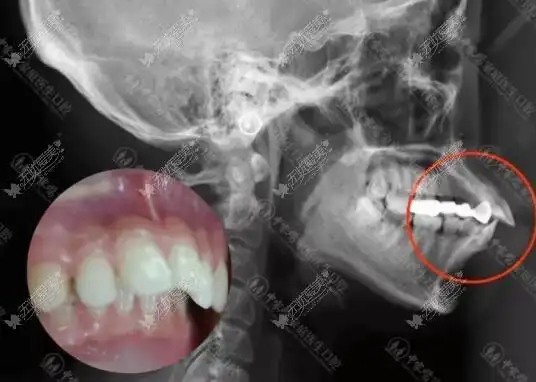

我骨性龅牙内收7毫米前后对比图片正畸正颌后嘴型变化挺大